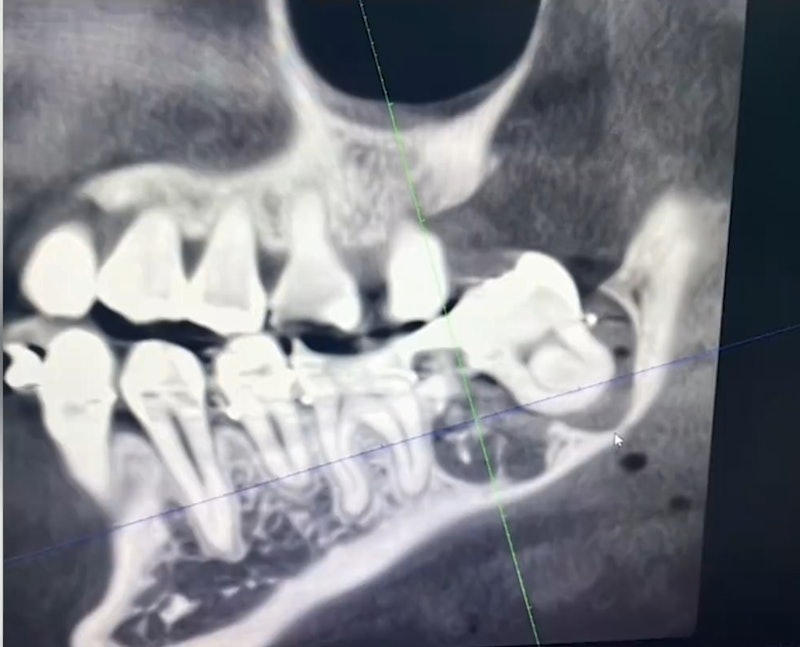

Ảnh chụp X-quang cho thấy bệnh nhân đã bị nhổ nhầm răng

Gia đình đã nhiều lần tìm đến bệnh viện để yêu cầu giải quyết nhưng không thành. Phải đến khi nạn nhân chụp phim tại một bệnh viện khác, sự thật mới được phơi bày.